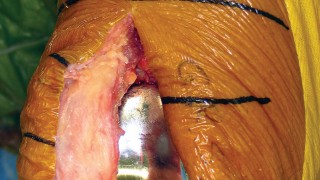

يركز هذا النهج على استخدام فتحة المفصل شبه الرضفية الإنسية المحدودة (Limited Medial Parapatellar Arthrotomy) وشق العضلة الرباعية المحدود، وهو جزء من مجموعة من الأساليب المعدلة التي توفر وصولاً ورؤية محدودين، ولكن يمكن تحويلها إلى نهج تقليدي إذا لزم الأمر. هذا يعني أن الجراح يمكنه البدء بتقنية أقل توغلاً، مع الاحتفاظ بالقدرة على التكيف إذا كانت الحالة تتطلب رؤية أوسع.

كيف يؤثر التدخل الجراحي المحدود على الأنسجة

تقليل طول الشق الجلدي:

مما يقلل من الندوب ويحسن المظهر الجمالي.

تقليل تضرر الأنسجة الرخوة:

عن طريق العمل من خلال "نافذة" جراحية أصغر، يتم تقليل التلاعب بالأنسجة والأربطة المحيطة، مما يقلل من النزيف والتورم والألم بعد الجراحة.